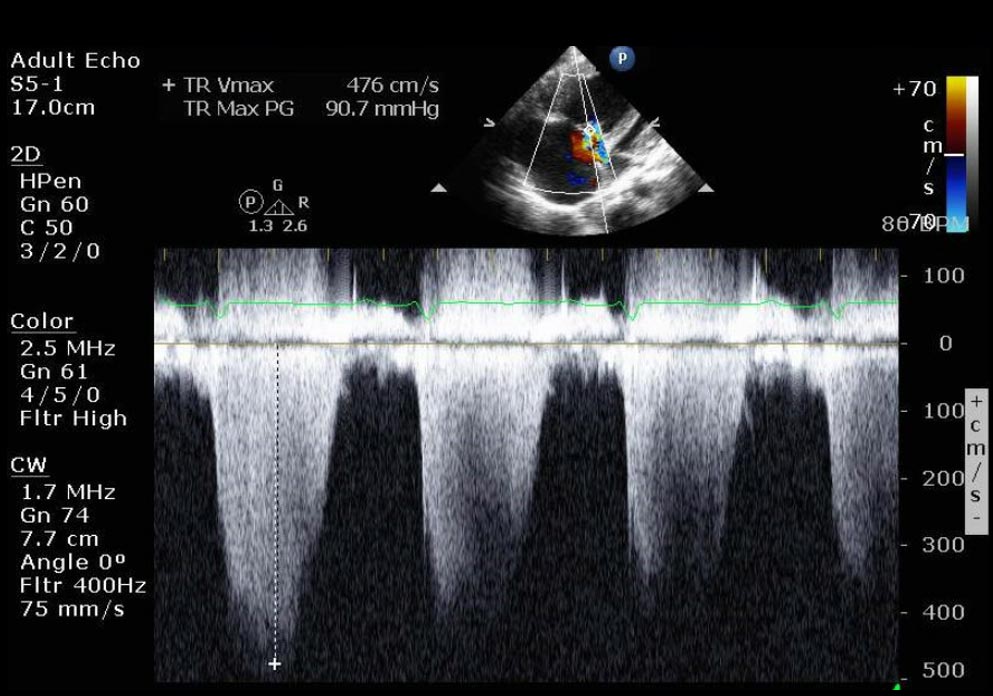

Echo imaging reveals right heart dilation

Echo provides essential visualization of right heart changes, aiding in detecting right heart dilation and dysfunction as the disease progresses.4,9

A doppler view of systolic pulmonary artery pressure with right dilation from PAH

Images courtesy of Anjali Vaidya, MD, FACC, FASE, FACP. Pulmonary Hypertension, Right Heart Failure & CTEPH Program, Temple University Hospital.

Doppler: Systolic pulmonary artery pressure

• RA pressure estimated to be 15 mm Hg due to noncompressible dilated inferior vena cava

• Systolic pulmonary artery pressure: 96 mm Hg